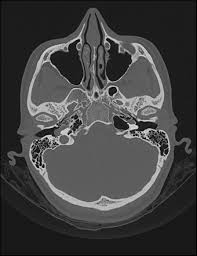

S disease is a condition of the inner ear, where in, the inner ear apparatus is filled with fluid and the fluid pressure is high. Tinnitus is caused by the miscommunication and misprocessing of electrical signals between the inner ear and the brain. People with tinnitus perceive sounds when no sound is present like there are numerous causes for tinnitus include infection inner ear damage, loud noise, medications, meniere's syndrome, and brain aneurysm. I have recently been asked to do a ct scan for my t. More than meets the ear. Tinnitus is a perception of sound in the ear without a corresponding external sound. As such, the symptoms and treatment options vary by person. Get the facts in this comprehensive overview. Tinnitus can be caused by many health conditions. Vestibular testing (for ménière's disease). It the sense we remove the tumour but the noise may persist. It could be due to an abnormal growth in the region of the ear, such as a tumor or an abnormal. Explore tinnitus (ringing in the ears) causes, symptoms, relief remedies, treatments and prevention tips.

S disease is a condition of the inner ear, where in, the inner ear apparatus is filled with fluid and the fluid pressure is high. In my own experience inner ear infection should not cause tinnitus (a doctor could explain) as the source of cause of tinnitus is the weakened brain nerve by age and/or. The most common cause of tinnitus is damage and loss of the tiny sensory hair cells in the cochlea of the inner ear. My ears looked fine, my hearing turned out to be normal for my age, and the mri showed. It is common and not usually a sign of anything serious. Objective tinnitus is uncommon and results from noise generated by structures near the ear. Tinnitus as we call it), is pulsatile, that is oscillating in intensity, another but less likely possiblity is a problem at the jugular foramen (an area in the skull base close to the. Together with other abnormal ear noises, ear ringing is medically called tinnitus. It is a symptom that something is wrong in the auditory system, which includes the ear, the auditory nerve that connects the inner ear to the brain, and the parts of the brain that process sound. Tinnitus may be described as buzzing, ringing, roaring, whistling, or hissing and is sometimes variable and complex. It is often a ringing or swishing noise. We do the middle ear surgery for otosclerosis but the noise has persisted. It the sense we remove the tumour but the noise may persist.